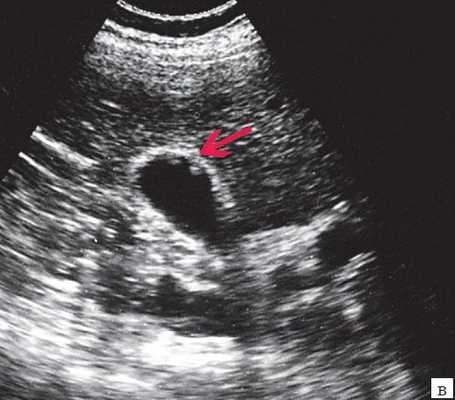

- УЗИ желчного пузыря. Эхогенная картина не слишком специфична и достаточно изменчива. На мониторе можно увидеть изменение структуры, толщины стенок, значительное увеличение объема пузыря. Внутри органа визуализируется скопление желчи, возможно с газовыми пузырьками, неоднородным осадком, хлопьями. В перипузырном пространстве обнаруживается выпот и скопление жидкости.